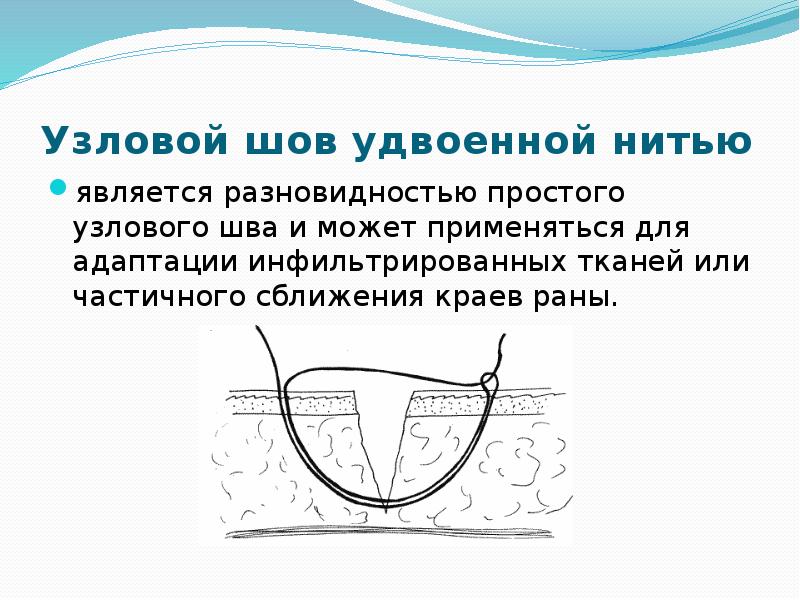

- 28. Узловой шов удвоенной нитью является разновидностью простого узлового шва и может